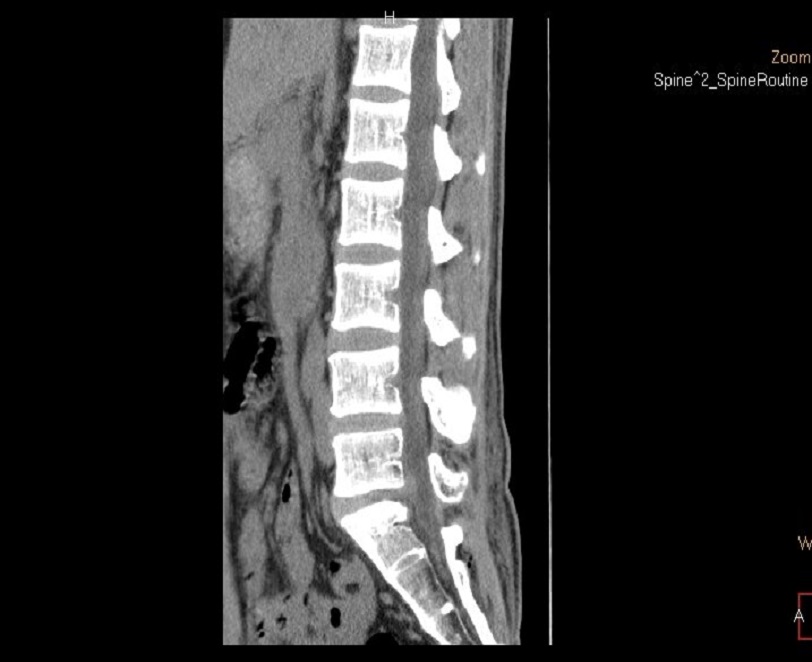

术后